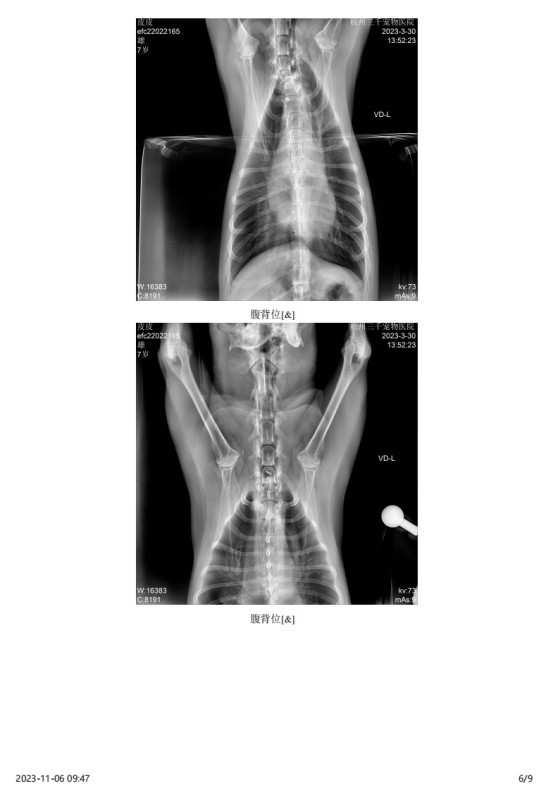

2023 年 3 月份检查结果